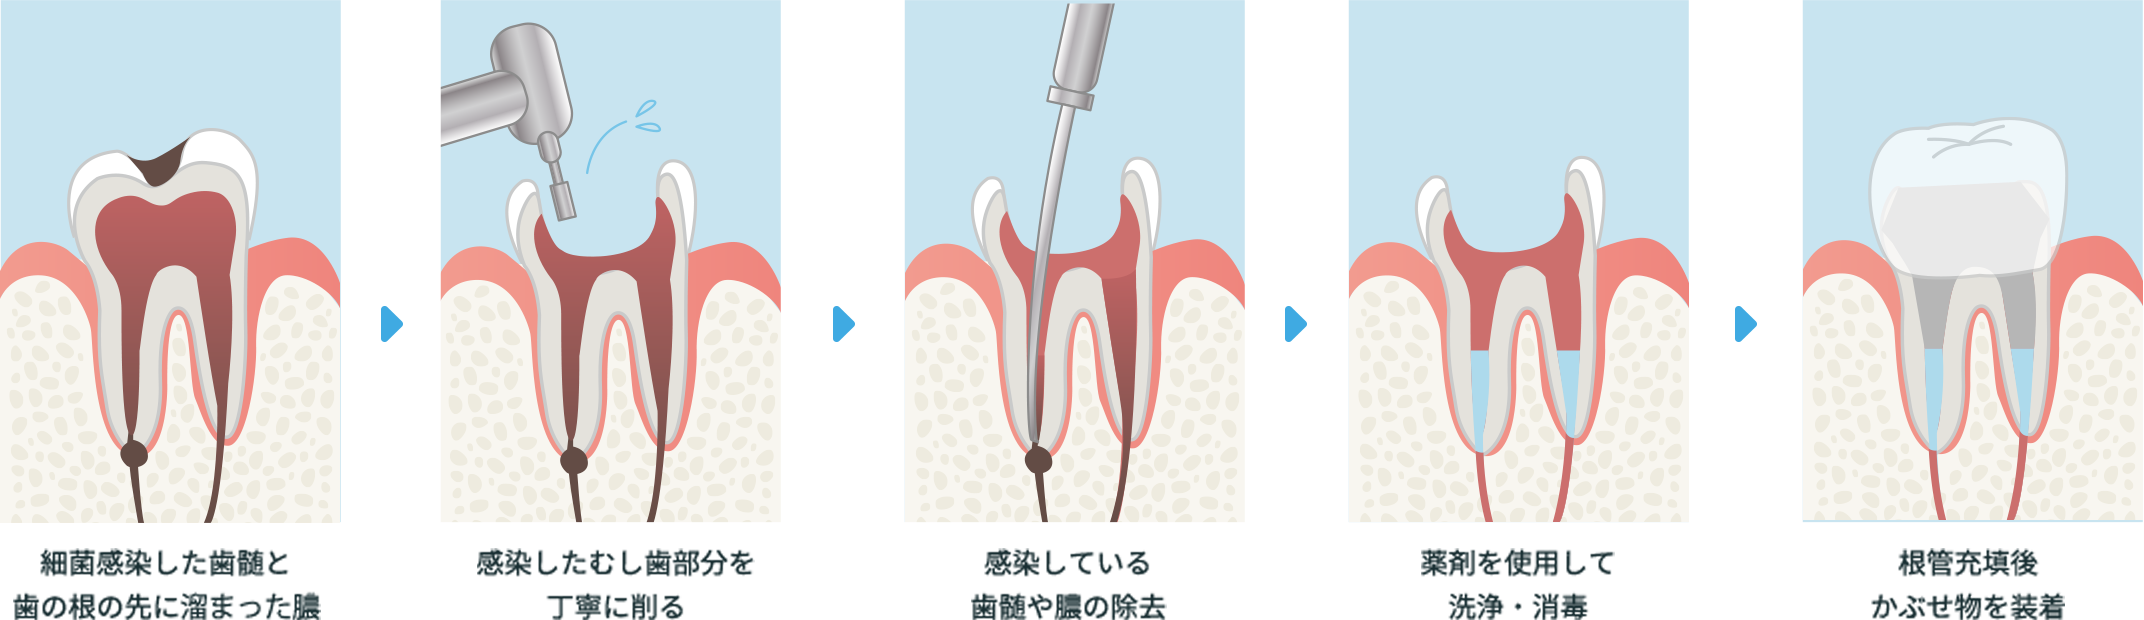

根管治療

歯の中には「歯髄(しずい)」と呼ばれる神経や血管を含む組織があります。むし歯が進行して歯髄が感染したり、壊死したりすると歯髄を取り除く根管治療が必要になります。これを一般的に「神経を抜く」と表現します。

横スクロールで確認いただけます。